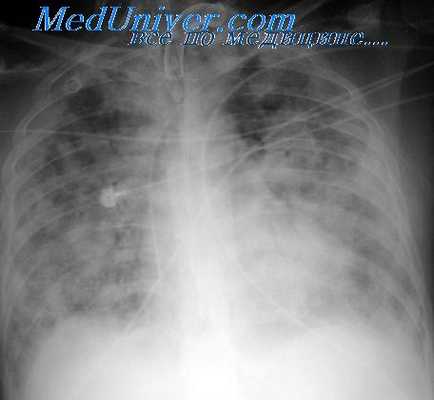

- Легкие – обструкция капиллярного русла, ателектазы, инфаркты и абсцессы, пневмофиброз

- Дыхание частое, поверхностное, кашель с кровохарканьем

- Пульс частый слабый, аритмичный; АД снижено

Сердечно-сосудистые и дыхательные симптомы обнаруживаются при тяжелой форме и достигают наибольшей выраженности при летальном варианте заболевания. Определяется слабость, бледность, одышка, интенсивная боль в груди, кашель, падение АД. При прогрессировании симптоматики развивается отек легких, дыхание становится частым, поверхностным, пульс замедляется, кожные покровы приобретают синюшный или бледно-серый оттенок. Возможны инфаркты легких и миокарда. Летальная форма сопровождается острой сердечной недостаточностью, асфиксией вследствие блокады легочного кровообращения либо нарушения регуляции дыхания продолговатым мозгом.

Респираторная форма болезни декомпрессии, известная водолазам, как приступ удушья, возможно, является результатом эмболии легких газовыми пузырьками. Патогномоничным будет резкое прерывание дыхания при ингаляции. Иногда впервые это выявляется в тот момент, когда водолаз на поверхности закуривает сигарету. Респираторная форма болезни декомпрессии часто появляется рано: это может произойти в течение первых минут тяжелой декомпрессии. Данное состояние также относится и к ранее описанным недомоганию и физической слабости после декомпрессии и их возможной взаимосвязи с субклинической формой эмболии легких. Известно, что около 2% всех случаев II типа болезни декомпрессии у водолазов сопровождается приступом удушья; у кессонных рабочих частота появления этого симптома приблизительно равна 6%.